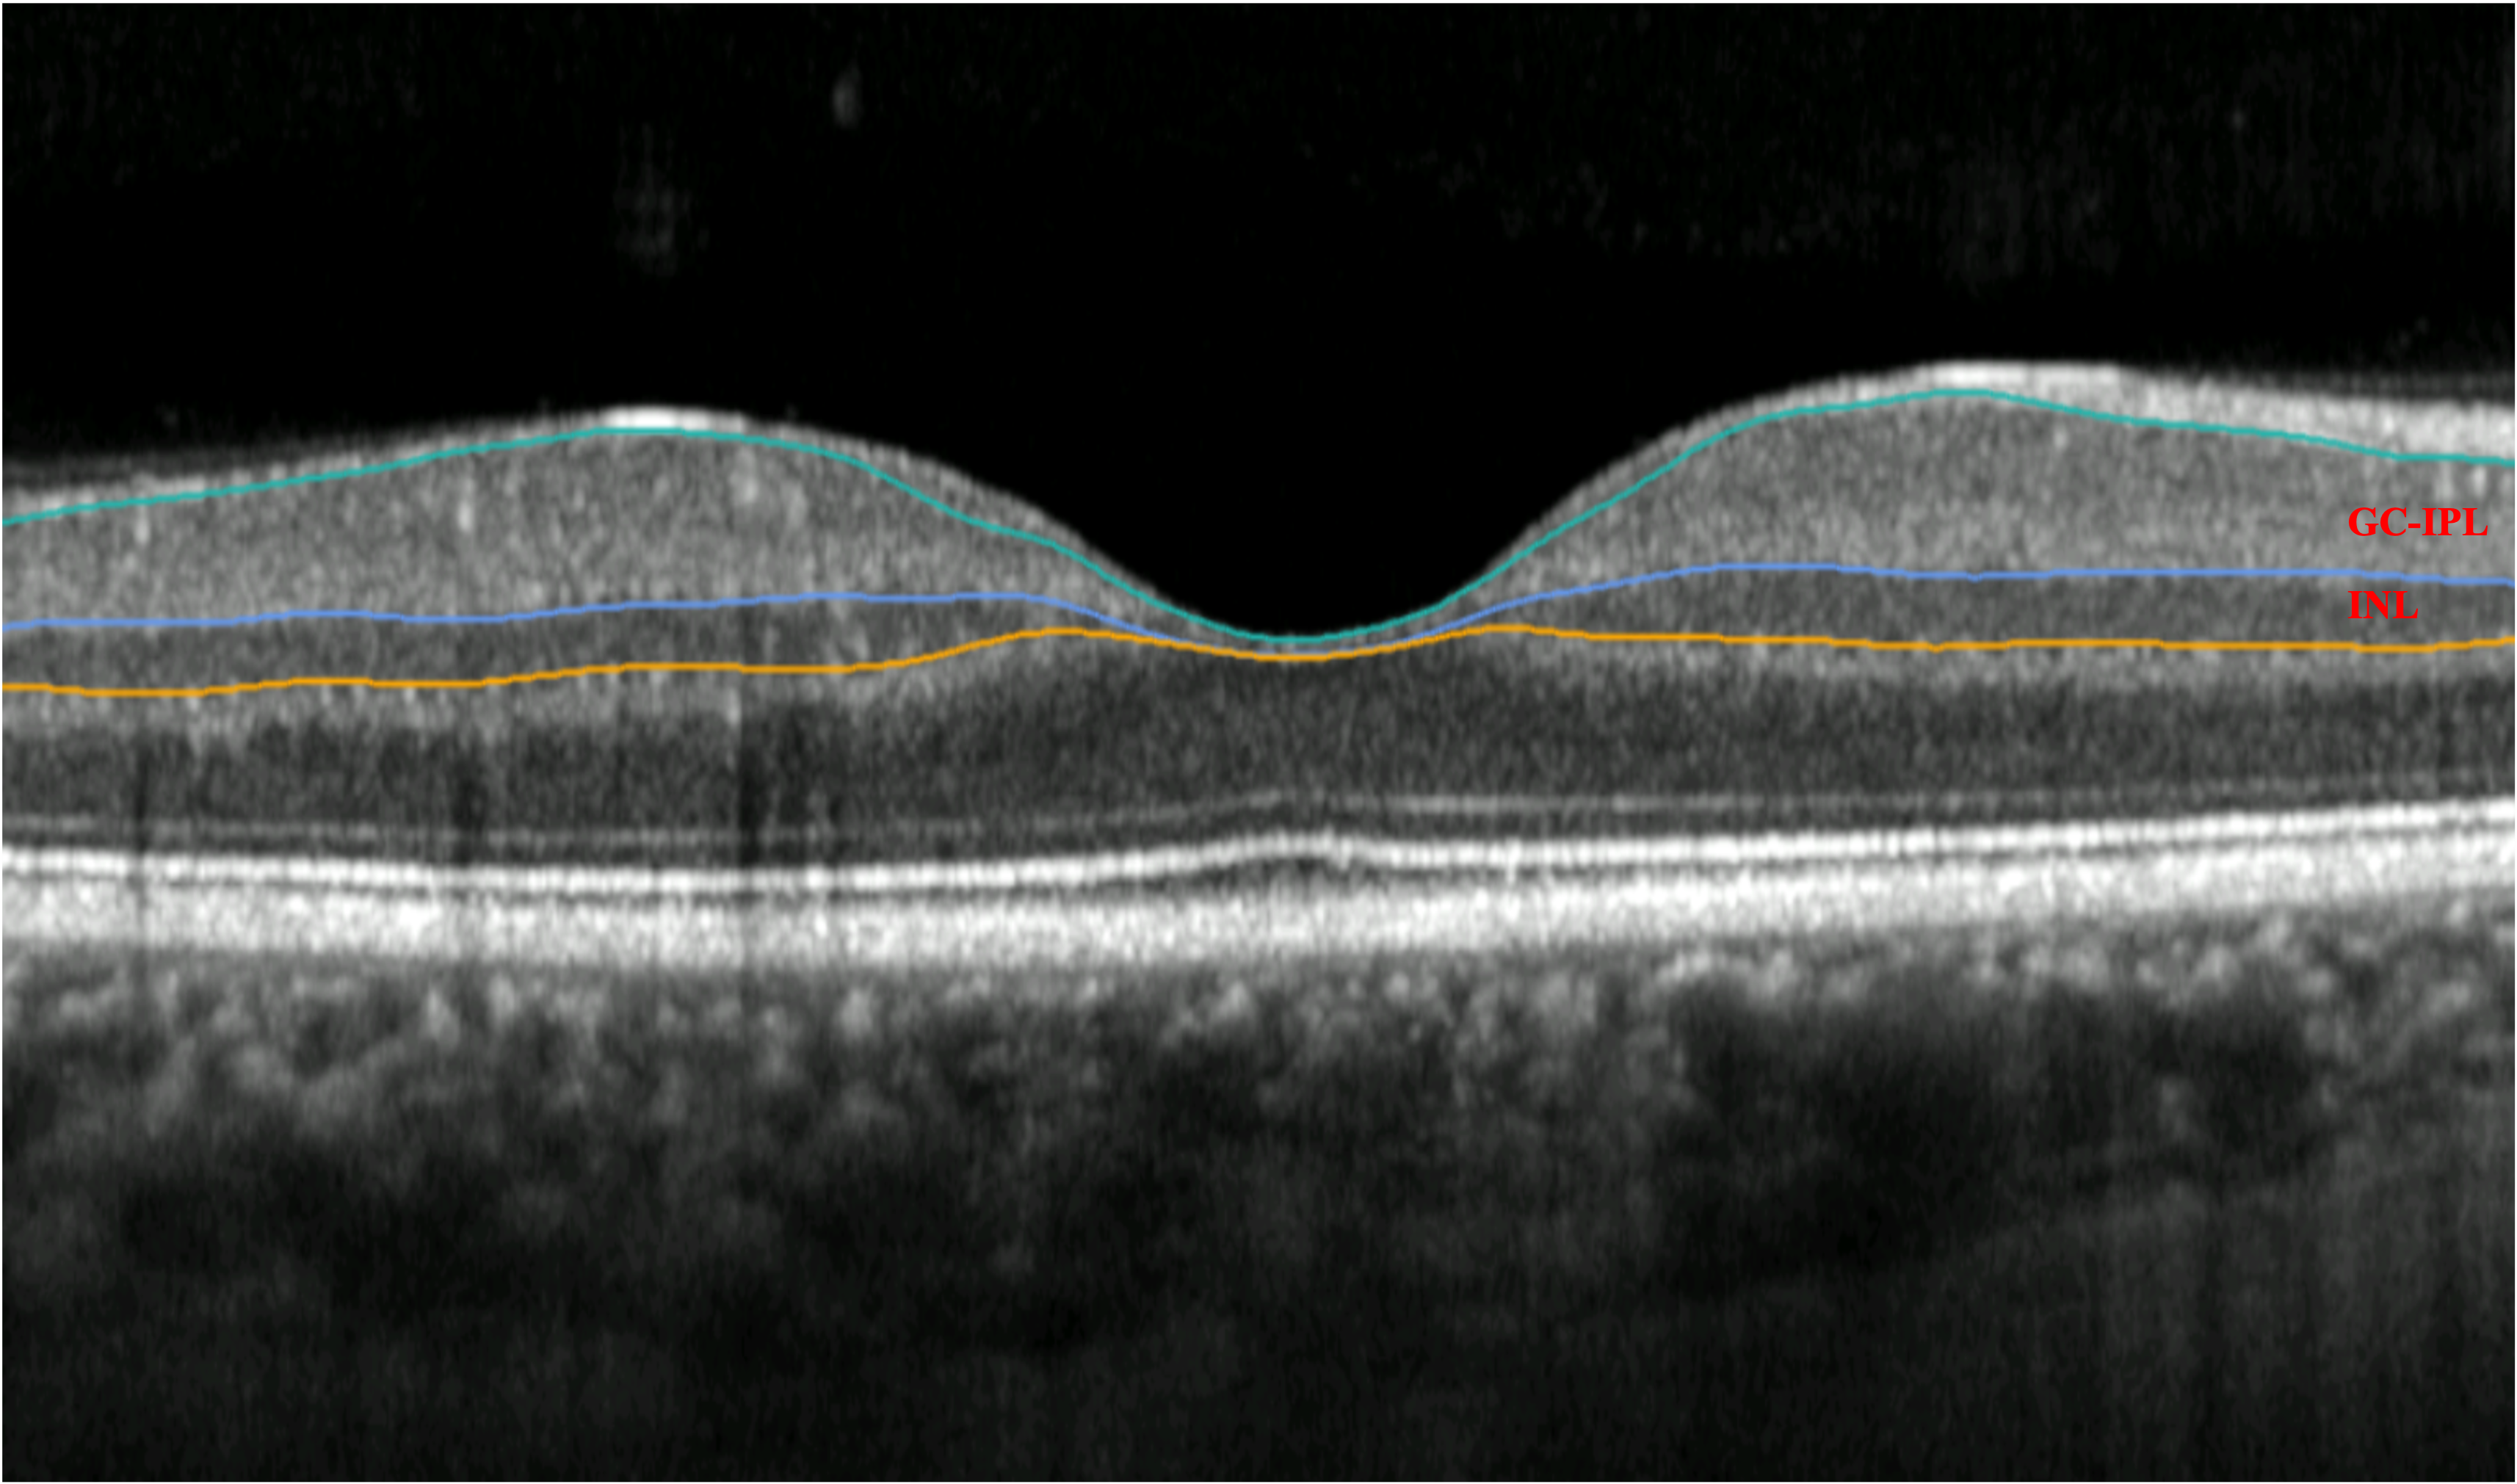

David Szanto, a medical student at Stony Brook, and working with the Department of Neurology at the Icahn School of Medicine at Mount Sinai, describes how an algorithm finds recurring patterns in the visual fields and the ganglion cell-inner plexiform layer thicknesses, and helps clinicians understand how prevalent those patterns are throughout the entire data.

Imaging biomarkers are useful to determine the degree of EZ attenuation in the fovea.